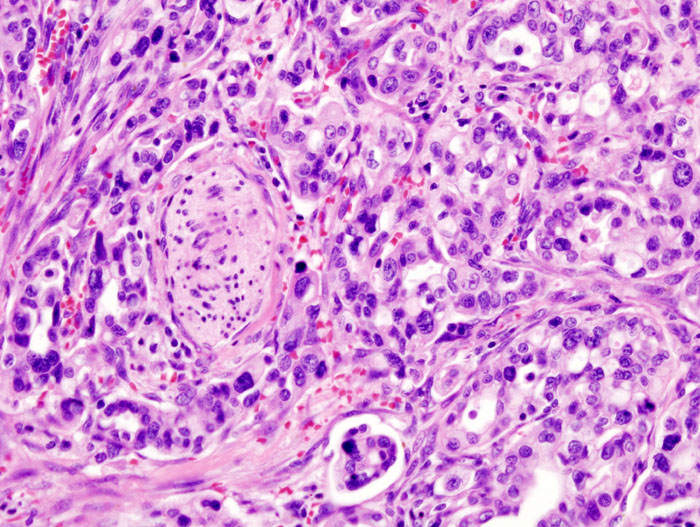

Crediti immagine: Wikimedia Commons. Licenza: CC attribution-sharealike 3.0 unported

Il gruppo di ricerca ha così osservato che in ogni campione di tessuto sano di pancreas erano presenti diversi gruppi di cellule che sono a tutti gli effetti dei precursori di un tumore (PANcreatic Intraepithelial Neoplasia, PanIN, ma per semplicità li chiameremo precursori) a carico delle cellule duttali. In pratica, una descrizione dettagliata dal punto di vista morfologico degli istanti iniziali di quelli che potrebbero un giorno diventare degli adenocarcinomi duttali.